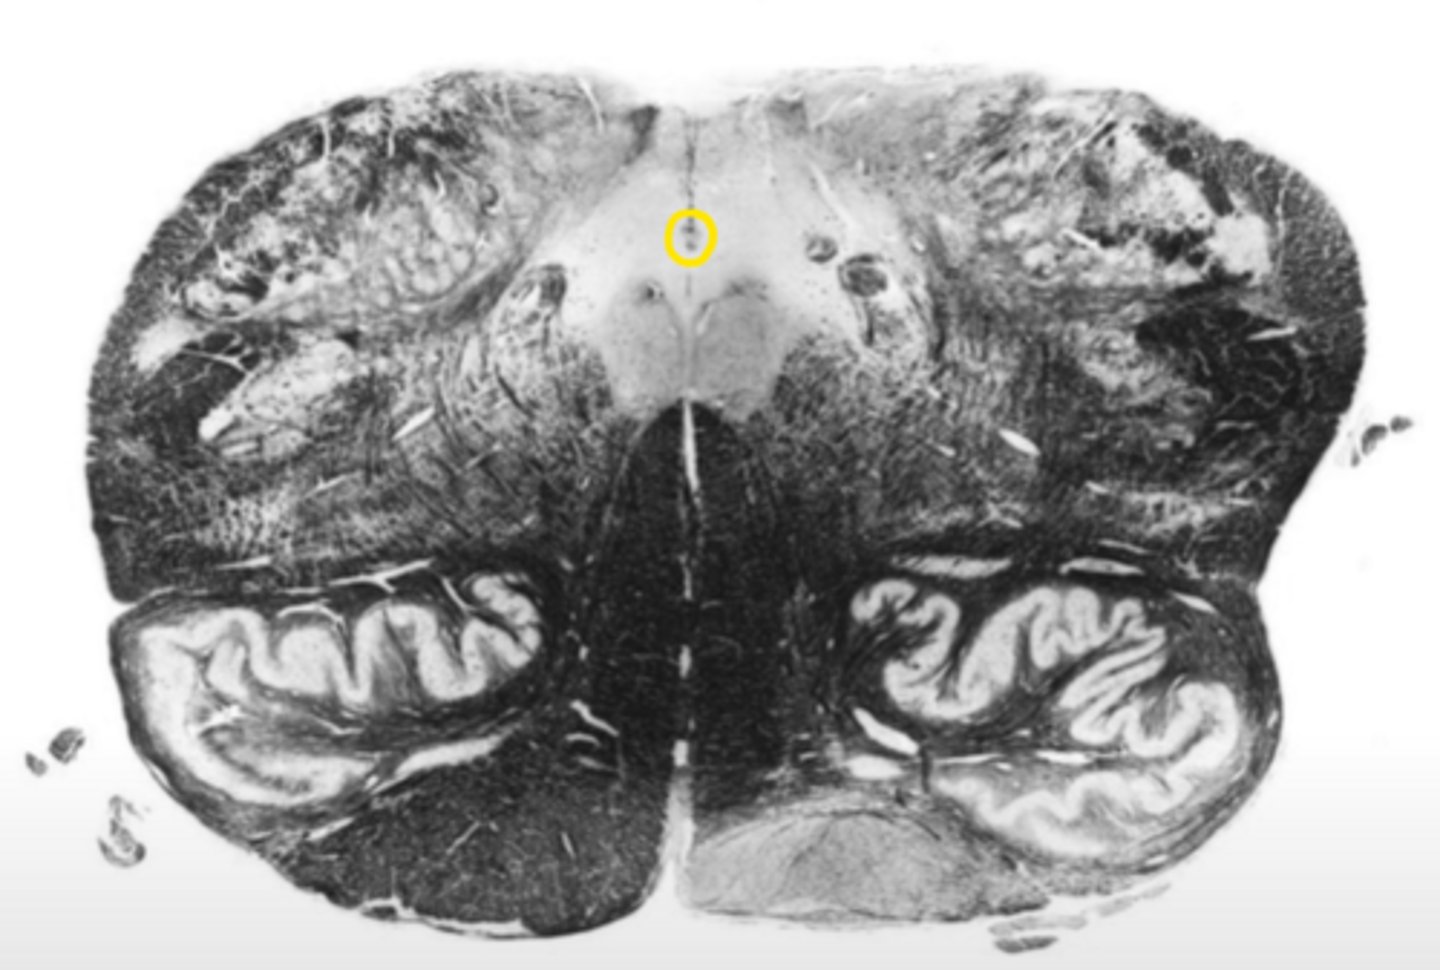

anterior median sulcus

ID the structure